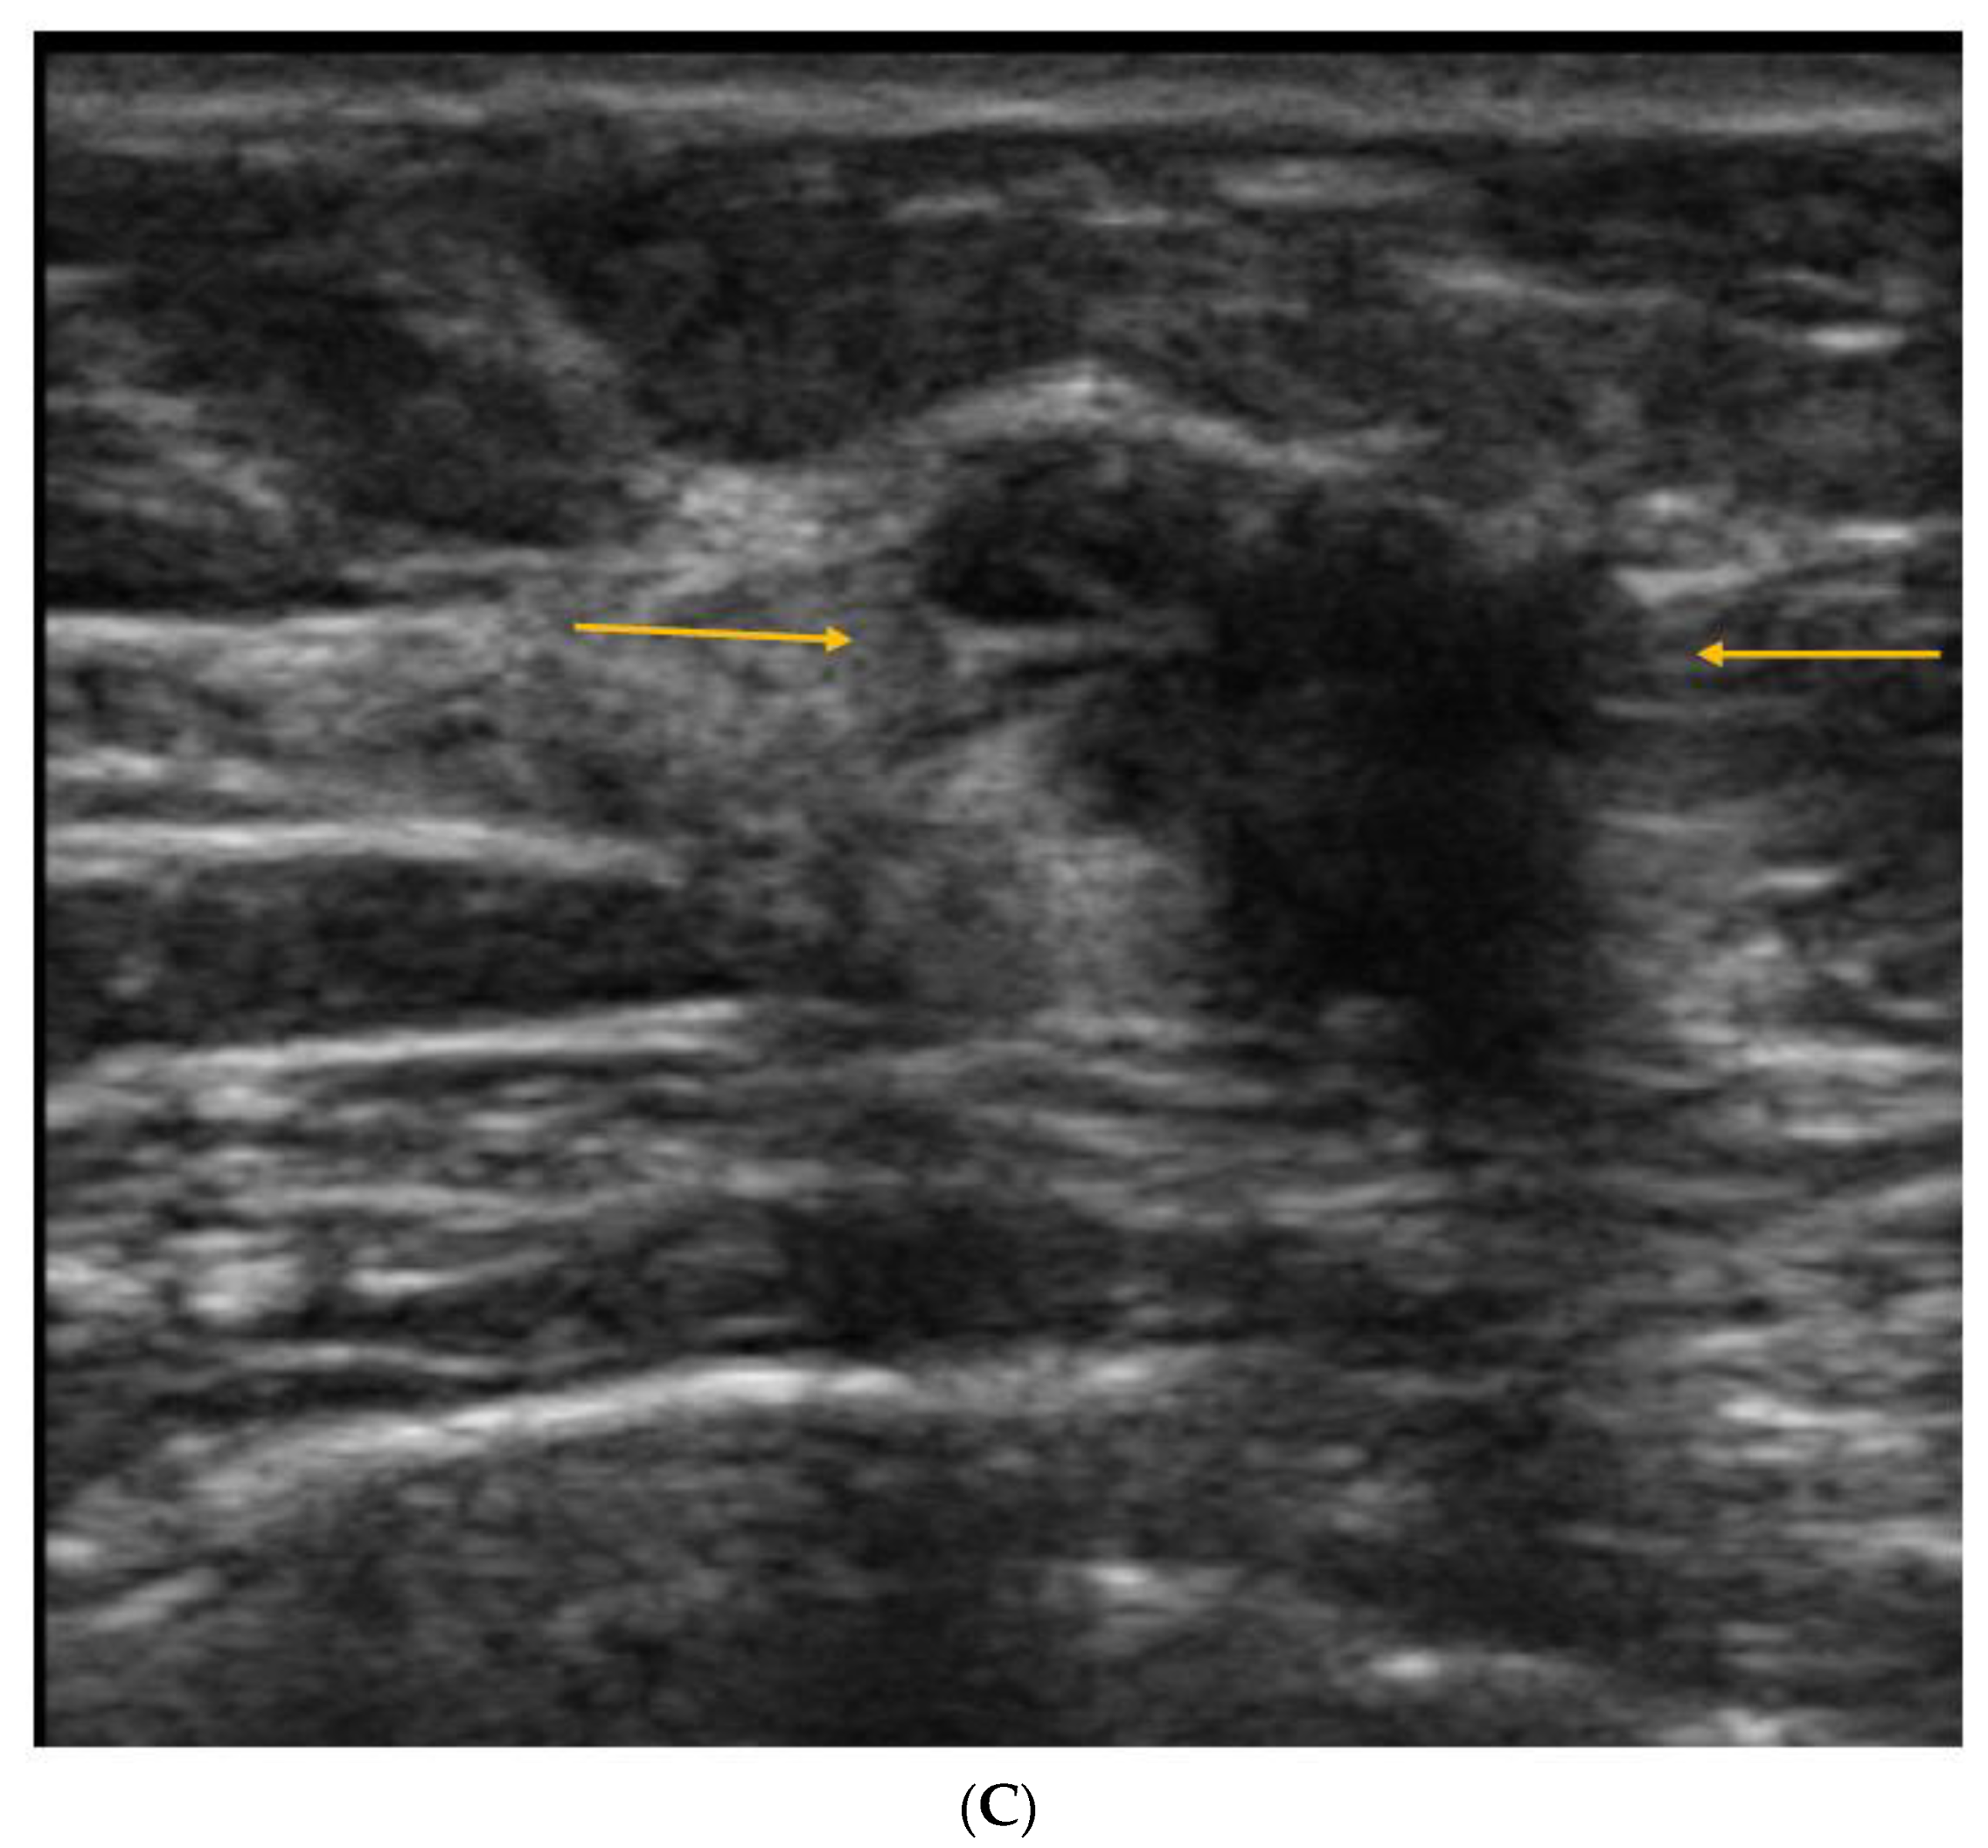

5. Ultrasound (US)